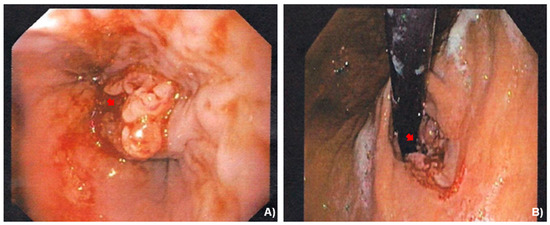

A 69-year-old female, with an unremarkable medical history, underwent an upper-GI endoscopy for progressive dysphagia for solid and liquids. A brittle ulcerous lesion with partial occlusion and signs of recent hemorrhage was detected at the EGJ with expansion to the lesser curvature of the gastric cardia, classified as a Siewert III tumor (Figure 1). The histopathological analysis of the endoscopic biopsies revealed a poorly differentiated invasive adenocarcinoma with HER-2 expression to be negative. The clinical staging included computed tomography (CT) (Figure 2) followed by a staging laparoscopy. Imaging demonstrated a locally advanced tumor (cT4) with a bulky locoregional lymph node packet (cN+) and three liver lesions consistent with hepatic metastases. In front of a possible oligometastatic state of disease, a staging laparoscopy took place to exclude peritoneal seeding and facilitate the application of a percutaneous feeding tube. During laparoscopy, macroscopic peritoneal seeding was excluded, while both the bulky lymph nodes at the lesser curvature and the largest liver metastasis at the left liver lobe could be visually detected (Figure 3). Remarkably, these tumorous lesions demonstrated a soft consistency in palpation with the laparoscopic forceps, which was not expected, as metastatic lesions from adenocarcinoma primary are anticipated to have a solid and hard texture. Therefore, a lymph node biopsy at the lesser curvature of the stomach was contacted in order to exclude different histopathology. The peritoneal cytology after collection of peritoneal washings proved to be negative.

Figure 1. (A,B) Initial gastroscopy findings depicting an ulcerous lesion at the gastroesophageal junction and (C,D) the lesser curvature of gastric cardia (yellow arrows).